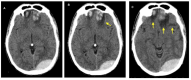

Cerebral edema is the abnormal accumulation of fluid in any of the tissue compartments of the cerebral parenchyma. It remains a significant challenge in neurotrauma care because it contributes to secondary brain injury, affecting prognosis. This review analyzes the recent literature, including foundational studies, to describe the mechanisms of distinct types of cerebral edema following traumatic brain injury (TBI). Emerging concepts, such as the role of the glymphatic system and heme-derived inflammasomes, offer new insights into new types of edemas, differentiated by pathogenesis and potential treatments. Recent advancements in understanding these molecular mechanisms can improve therapeutic strategies, facilitating a better approach in the era of precision and personalized medicine. Although there has been notable progress, a proposal to customize treatments for diverse types of edemas is necessary to improve outcomes following traumatic brain injury. In this review, we describe the current subtypes of post-traumatic brain edemas and link them to a specific management approach.